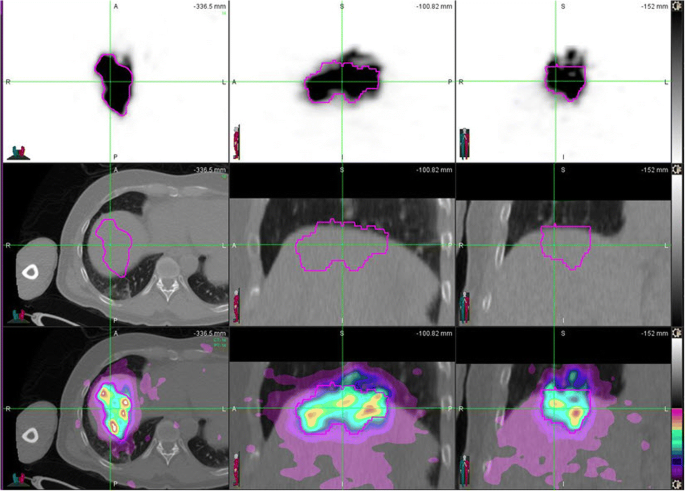

PET/MRI and PET/CT images of the subject with the highest mean liver dose difference of 18.5%. In the first row, there are PET images, in the second row MRI and CT images, respectively, and in the third row fused PET/MRI and PET/CT images, respectively. Due to different field of view and voxel sizes in PET/MRI and PET/CT, the size of the images is different for different modalities and different studies. However, the distribution of 90Y microspheres is practically identical. The mean liver dose obtained from PET/CT was 38.81 Gy and 31.64 Gy from PET/MRI. In PET/MRI image, left image, second row, one can clearly see the tumor and tumor ROI almost perfectly matches the most intense 90Y microsphere distribution

In our study, PET/MRI led to underestimation of the mean liver dose values by less than 10% on average, when compared to PET/CT. In some cases, PET/MRI values were almost the same or even slightly higher than PET/CT values. In our previous work [28], in which we compared MR-based and CT-based attenuation corrections on the same subjects, SUVmean and SUVmax values obtained from PET/CT were slightly higher in values than the corresponding values obtained from PET/MRI. It seems that the same trend is present in comparison of dosimetry values in 90Y post-therapy studies (Fig. 3). In both cases, the reason for the variation in these values lies in the difference of attenuation corrections applied. However, in this comparison, additional source of difference is also attributed to creation of ROIs from CT and MRI anatomic images, which were used for dosimetry calculations. In Fig. 2, one can see very small difference between PET/MRI and PET/CT ROIs. However, numerical results shows that liver volume determinate from PET/CT was 858.35 cm3 and from PET/MRI 801.28 cm3. This difference in volume determination and consequently the mass of liver, which is calculated by multiplying volume in cubic centimeter to 0.00103 kg/cm3, has great impact on dosimetry calculations. LDM assumes that all of the energy released by the 90Y beta-particle decay remains within the same voxel. Using the average energy of beta particles, the total energy deposited per unit volume over the entire isotope decay, which is assumed to be infinity due to the permanent implant of microspheres, can be calculated. Calculations give that in each voxel we can assume that the dose in Gy is equal to product of activity in GBq × 49.38/mass (kg) [29]. Here, we used corrected activity for any extra-hepatic distribution such as lung shunting and corrected for residual activity. In this particular case, where tumor was clearly visible in MRI images, we calculated tumor-to-normal tissue (T/N) dose ratio. For this purpose, we used MRI image with tumor ROI to merge with CT images from PET/CT, using deformable transformation provided by MIM software. Although it is beyond the scope of this paper, the T/N ratio in this particular case was 24.90 for PET/CT and 30.00 for PET/MRI study. However, both modalities resulted in a tumor volume about 7.0 cm3 and for such small tumors partial volume effects would greatly affect quantification and dosimetry calculations. The limitation of our approach was that we did not use contrast media in CT nor MRI images. Without contrast media, delineation of lesions and tumors in liver is difficult and not always accurate. Intra hepatic dosimetry, like calculations of T/N ratios, requires using of contrast in anatomical modalities, as well as, PV corrections for lesions smaller than 2.5 cm [19]. Also, for lesions in superior hepatic lobes (Fig. 4), respiratory motion effect can alter 90Y imaging and dosimetry and motion correction should be applied [25].